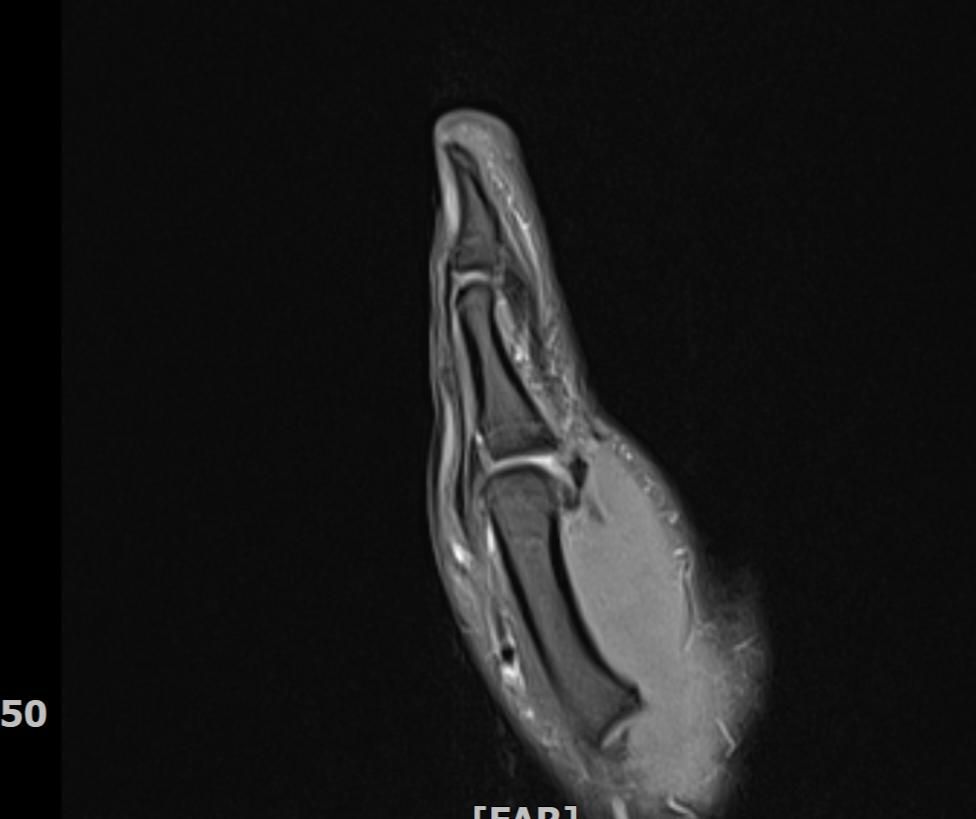

mri 엄지손가락 미세골절 여부확인

공구에 왼손이 말려서 엄지를 다쳤습니다 응급실에서 부목고정 조치후 이틀후 mri촬영 하였습니다.

엄지손가락 뼈가 자주 욱씬거리는데 미세골절 여부 확인 부탁드립니다.

• 1번 째 사진

우선 현재로썬 MRI 사진으론 정확한 판단을 하긴 어렵지만 주변 연부조직의 손상이 보여집니다.

다만 미세골절 같은 경우는 여러 방면의 판독이 필요하므로 정확한 판독은 병원에 내원하셔서 MRI 촬영을 한 병원에 판독지를 받으시고 전문의에 판독을 받으시길 적극 추천드립니다.